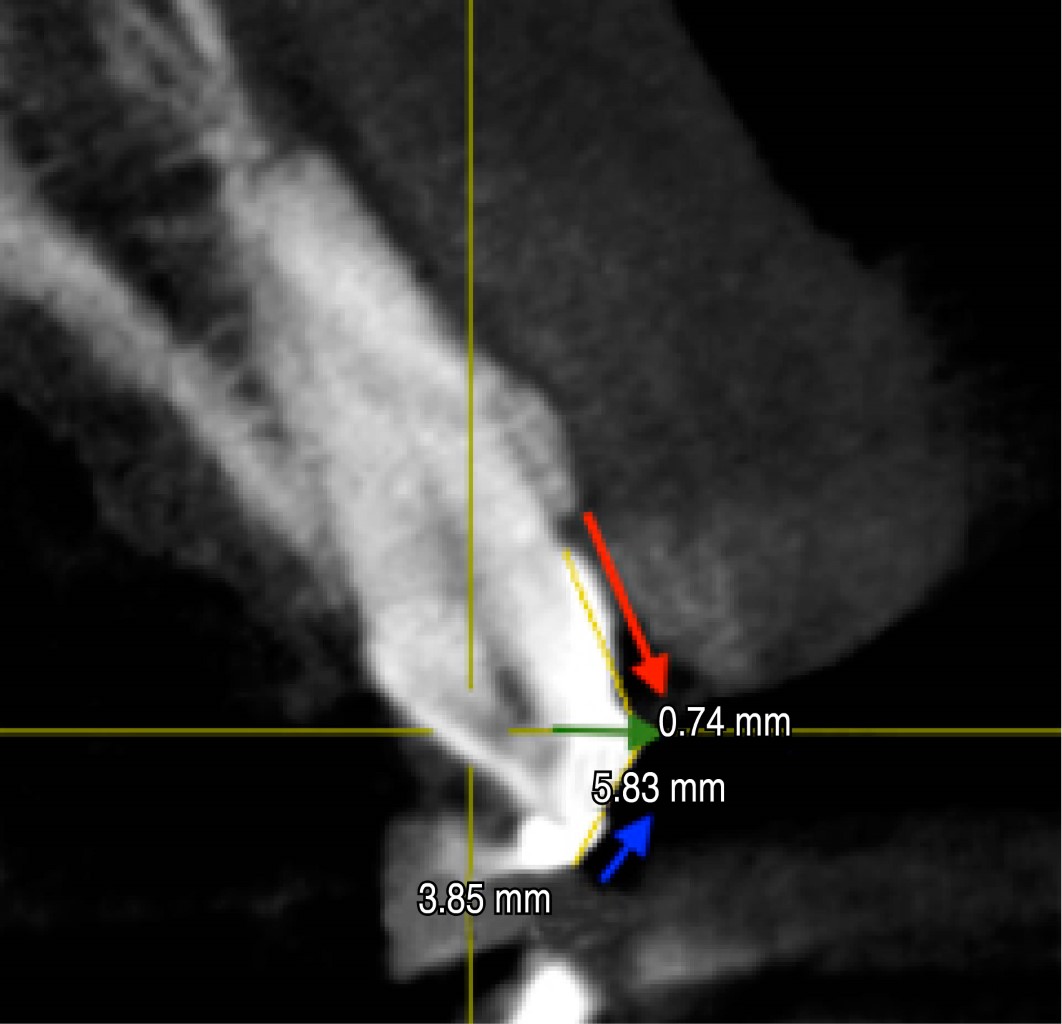

Se procede a medir las coronas clínicas del 1.3, 1.2, 1.1, 2.1, 2.2, 2.3 (nomenclatura FDI) con una sonda periodontal milimetrada [UNC-15 Hu-Friedy: 1 mm cada raya] (Figura 2), se toma la medida desde el margen gingival al borde incisal de cada órgano dental, se colocan varios puntos de resina fluida en cada pieza dental a nivel de la mitad de la corona clínica, con el fin de poder medir con precisión la curvatura convexa de la corona dental en la tomografía 3D [Orthophos XG 3d ready ceph/ Sirona] (Figura 3). Se procede a toma de la tomografía y posteriormente se realizan los trazos de las líneas para poder medir el tamaño real de la corona anatómica.

En el examen radiográfico tridimensional se procede a dividir la corona del diente en dos partes trazando dos líneas: Línea A (se mide en mm del tope de resina fluida al borde incisal [BI] del diente) y una Línea B (se mide en mm desde el UCE al tope de resina fluida), se suma la línea A más la línea B para dar como resultado la longitud de la corona dental (Figura 6) (Tabla 2).

A los resultados del CBCT de la longitud de la corona dental se le resta la medida del tope de resina, con el objetivo de tener como resultado el tamaño real de la corona anatómica. El tamaño del tope de resina de cada diente se logró midiéndolo en la tomografía 3D como se puede observar en la Tabla 3.

Se realizó un cuadro comparativo de las medidas de la corona clínica (sondeo periodontal) y la corona anatómica real (CBCT) de cada pieza dental anterior, restando ambos datos (sondeo-CBCT) con el propósito de obtener la cantidad precisa de tejido gingival a eliminar en la cirugía de alargamiento de corona (Tabla 4).

Se tomó la decisión de realizar la osteotomía y osteoplastia con el objetivo de dar el espacio al tejido supracrestal o espacio biológico (Tabla 5) (Figura 7 A y B) y así permitir una inserción del tejido conectivo y epitelio de unión; se tomó la referencia de Gargiulo y colaboradores donde el espacio biológico está formado por 0.97 mm de epitelio de unión y 1.07 mm de tejido conectivo, sumando 2.04 mm.14